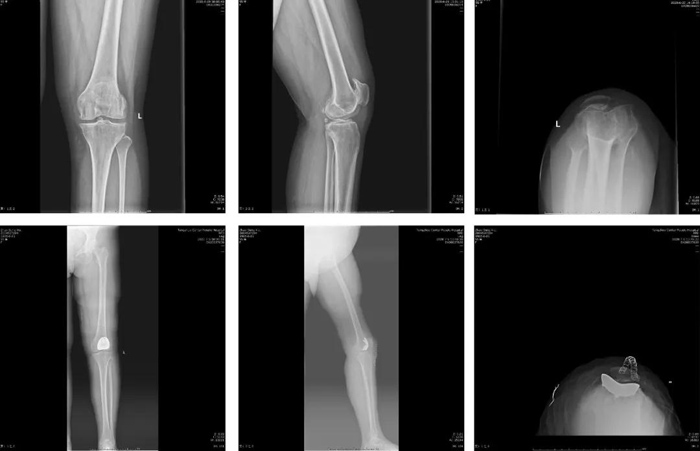

近日,我院關(guān)節(jié)運(yùn)動(dòng)一科率先完成魯南地區(qū)首例髕股關(guān)節(jié)置換術(shù)。

患者中年女性,55歲,因左膝關(guān)節(jié)疼痛7年,加重2年入院?;颊?/span>7年前無明顯誘因出現(xiàn)左膝關(guān)節(jié)疼痛,長距離行走或負(fù)重活動(dòng)后疼痛加重,休息后可緩解。2年前左膝關(guān)節(jié)疼痛加重,下蹲、上下樓梯困難,嚴(yán)重影響日常生活。

7月9日,患者在全麻麻醉下行左側(cè)髕股關(guān)節(jié)置換術(shù)。手術(shù)時(shí)間約30分鐘,術(shù)后患者麻醉清醒后即下床活動(dòng),膝關(guān)節(jié)屈伸功能及疼痛情況較全膝關(guān)節(jié)置換術(shù)明顯改善,術(shù)后第3天出院。門診隨訪目前患者膝關(guān)節(jié)功能鍛煉良好,無并發(fā)癥出現(xiàn),患者滿意度高。